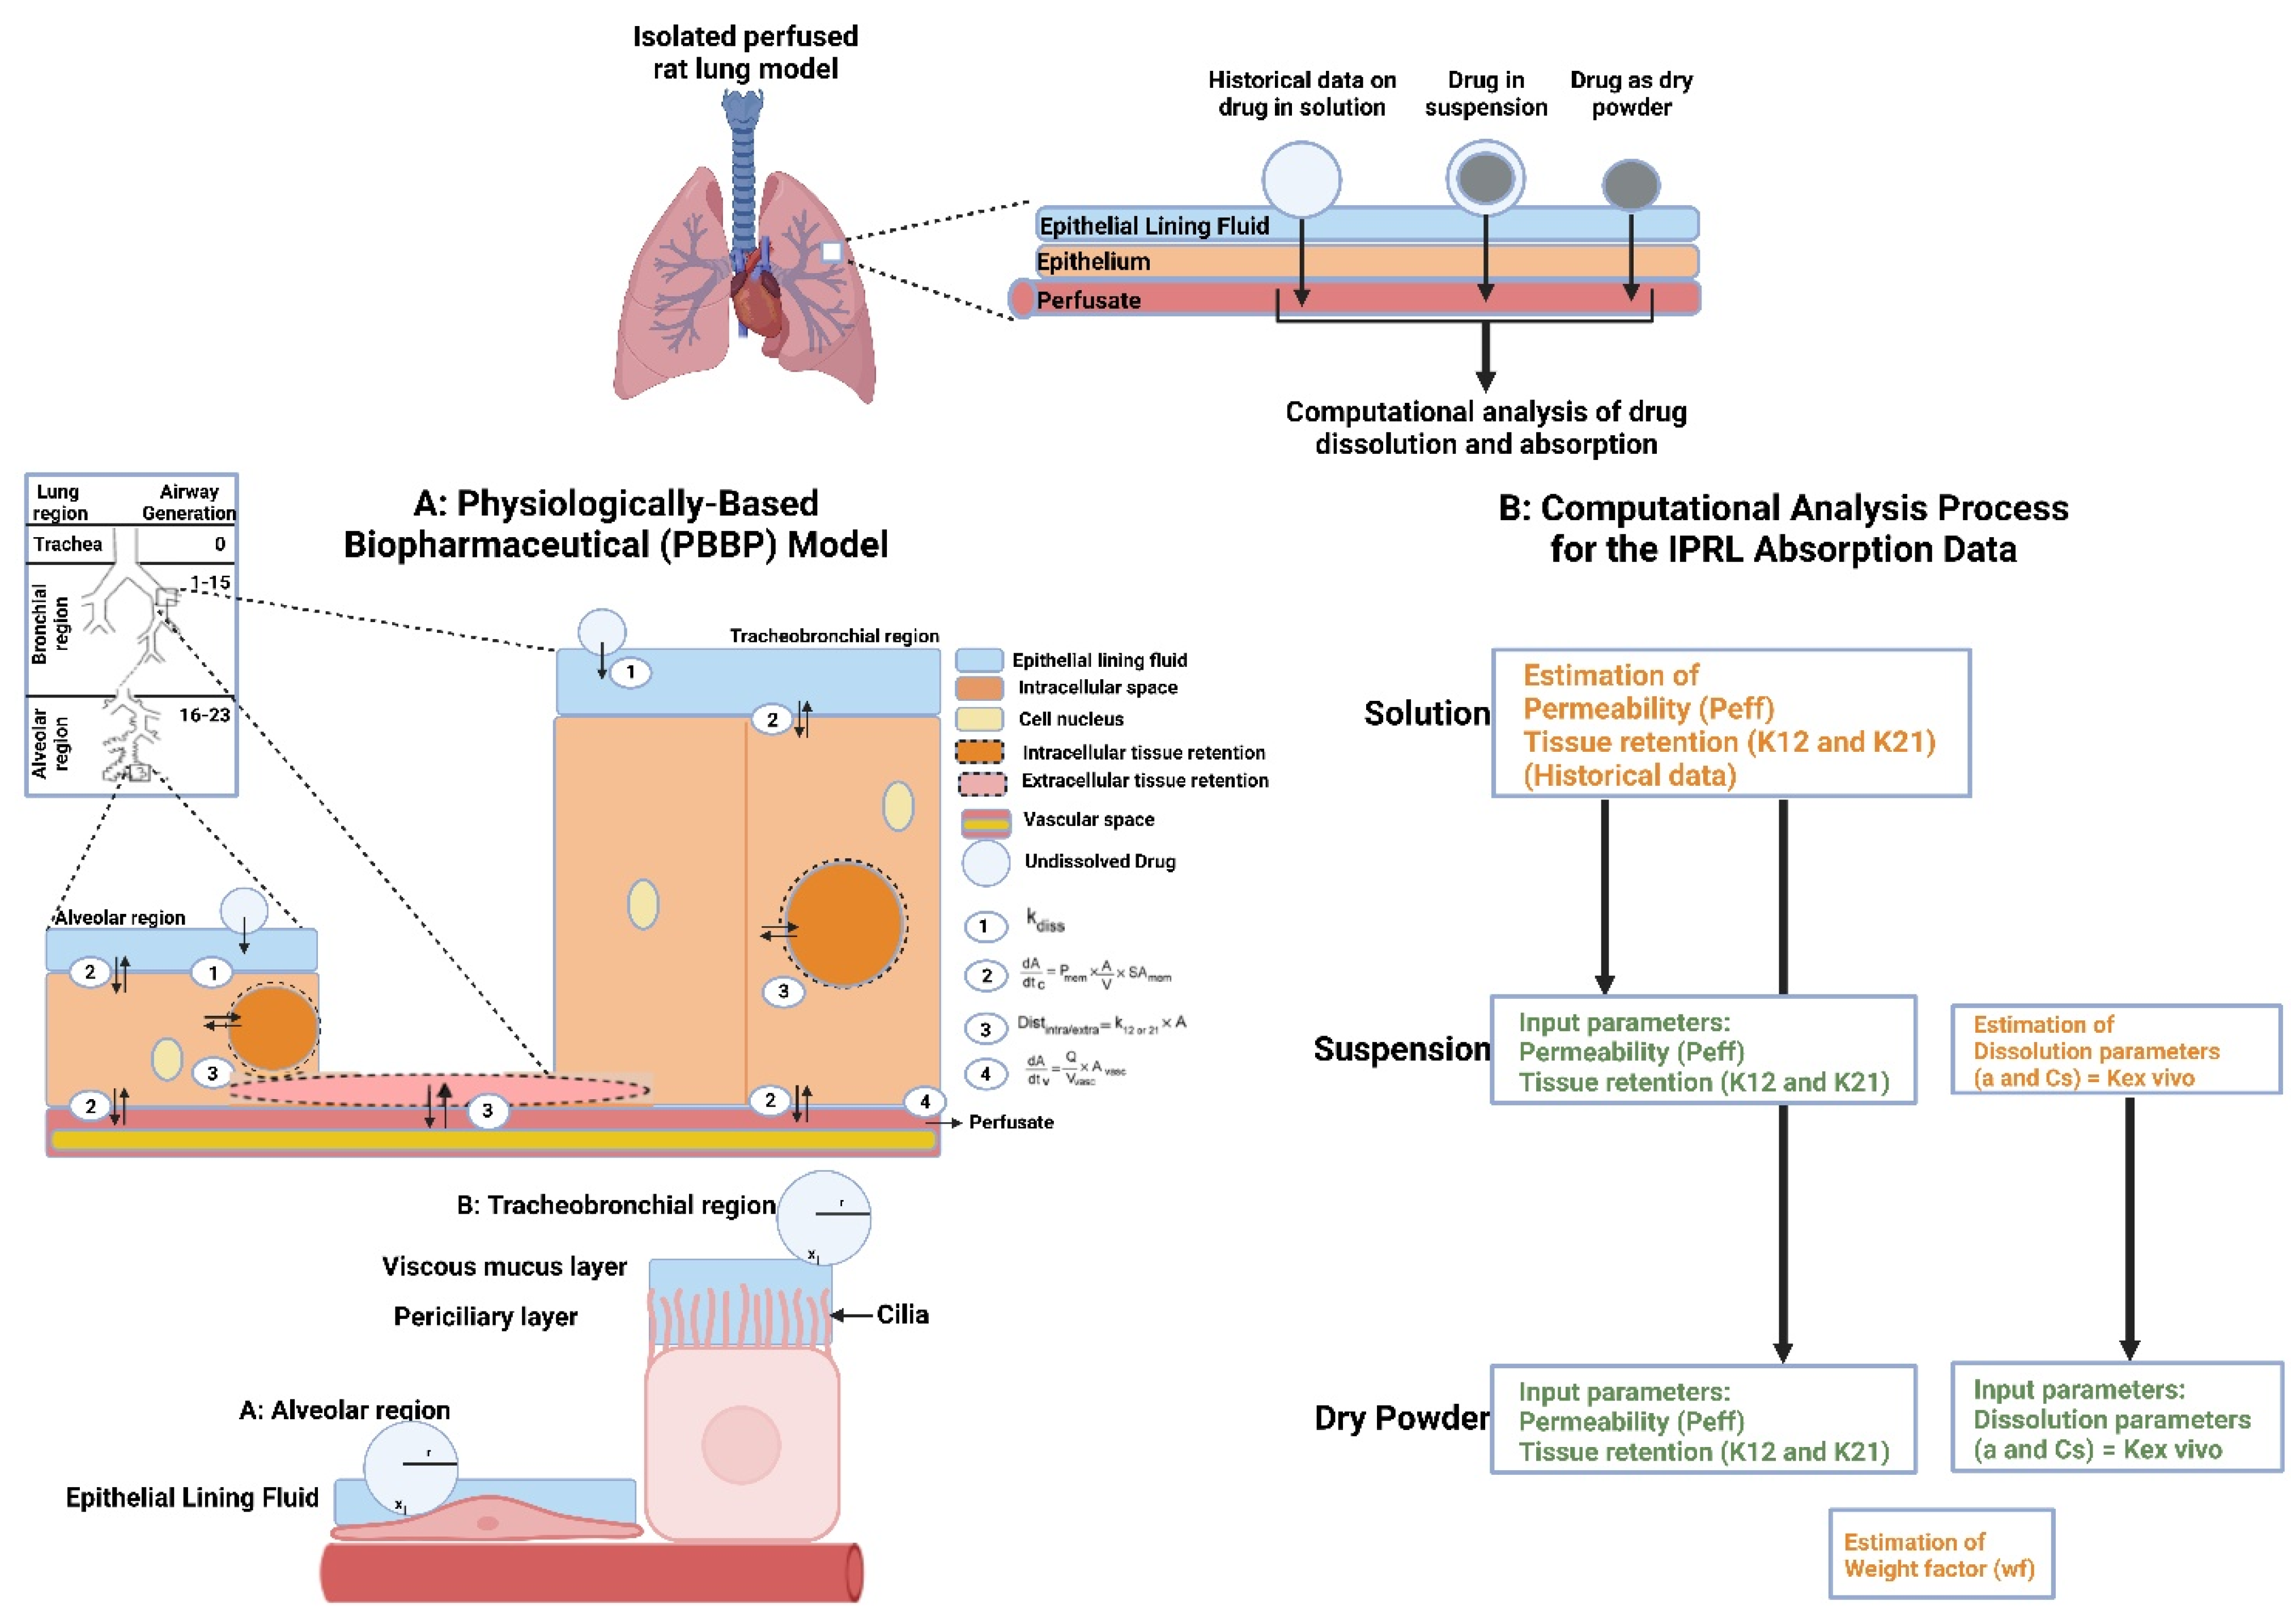

7.2. Ex Vivo Lung Tissue/Organ-Based Models